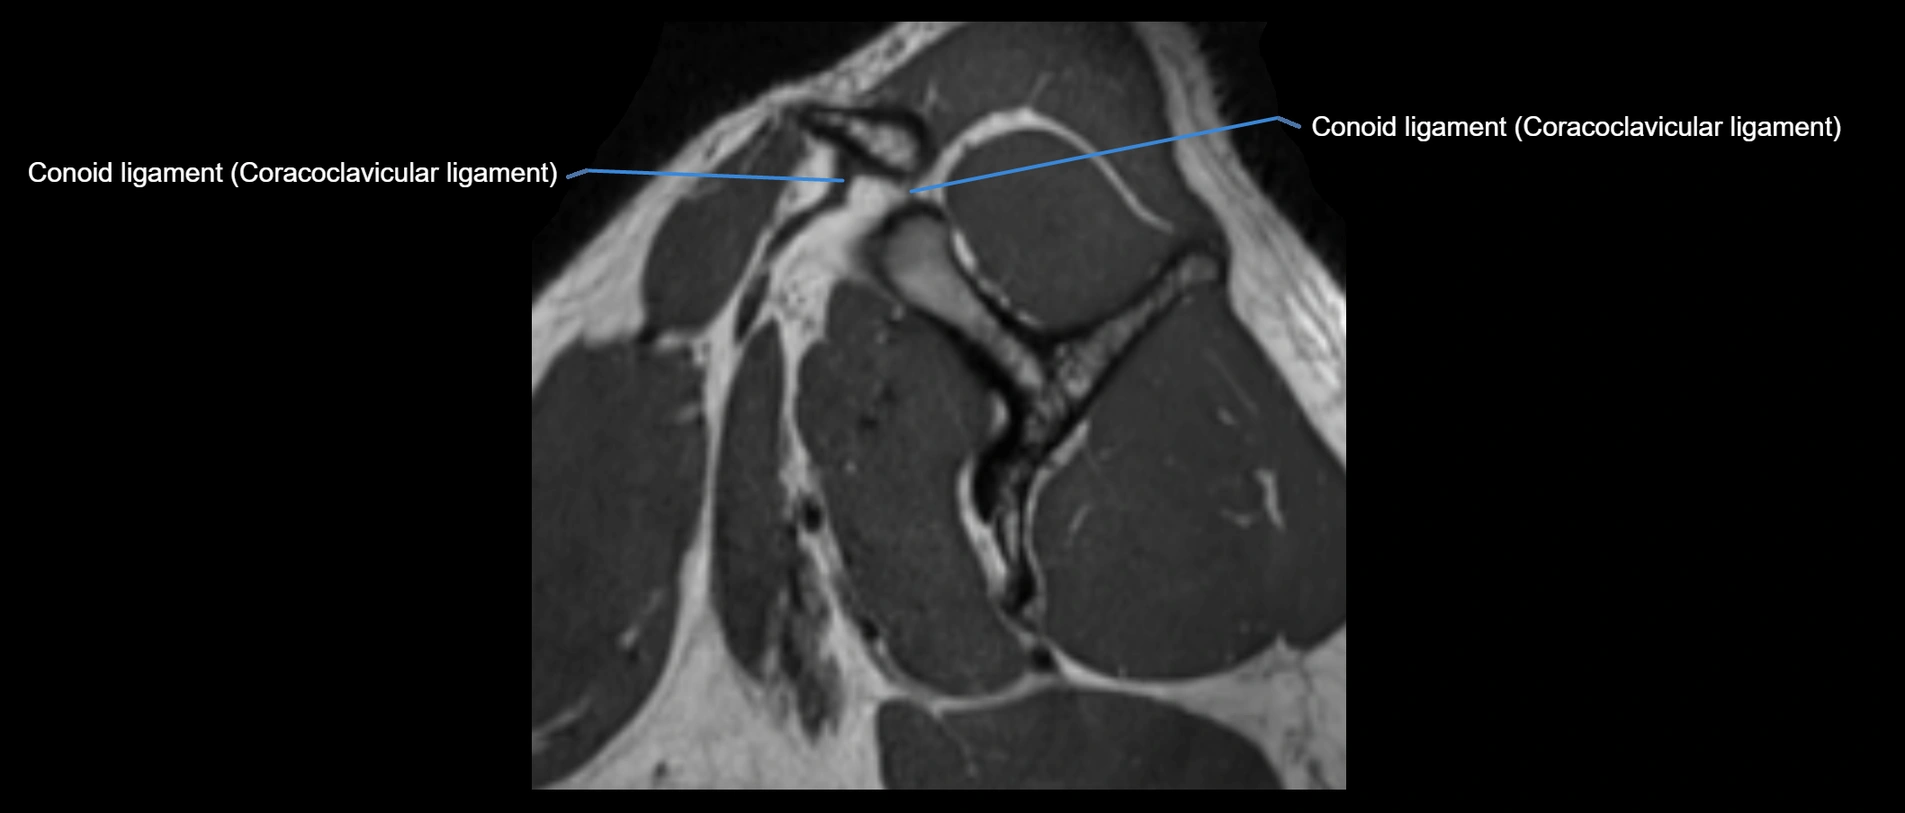

CT image

image